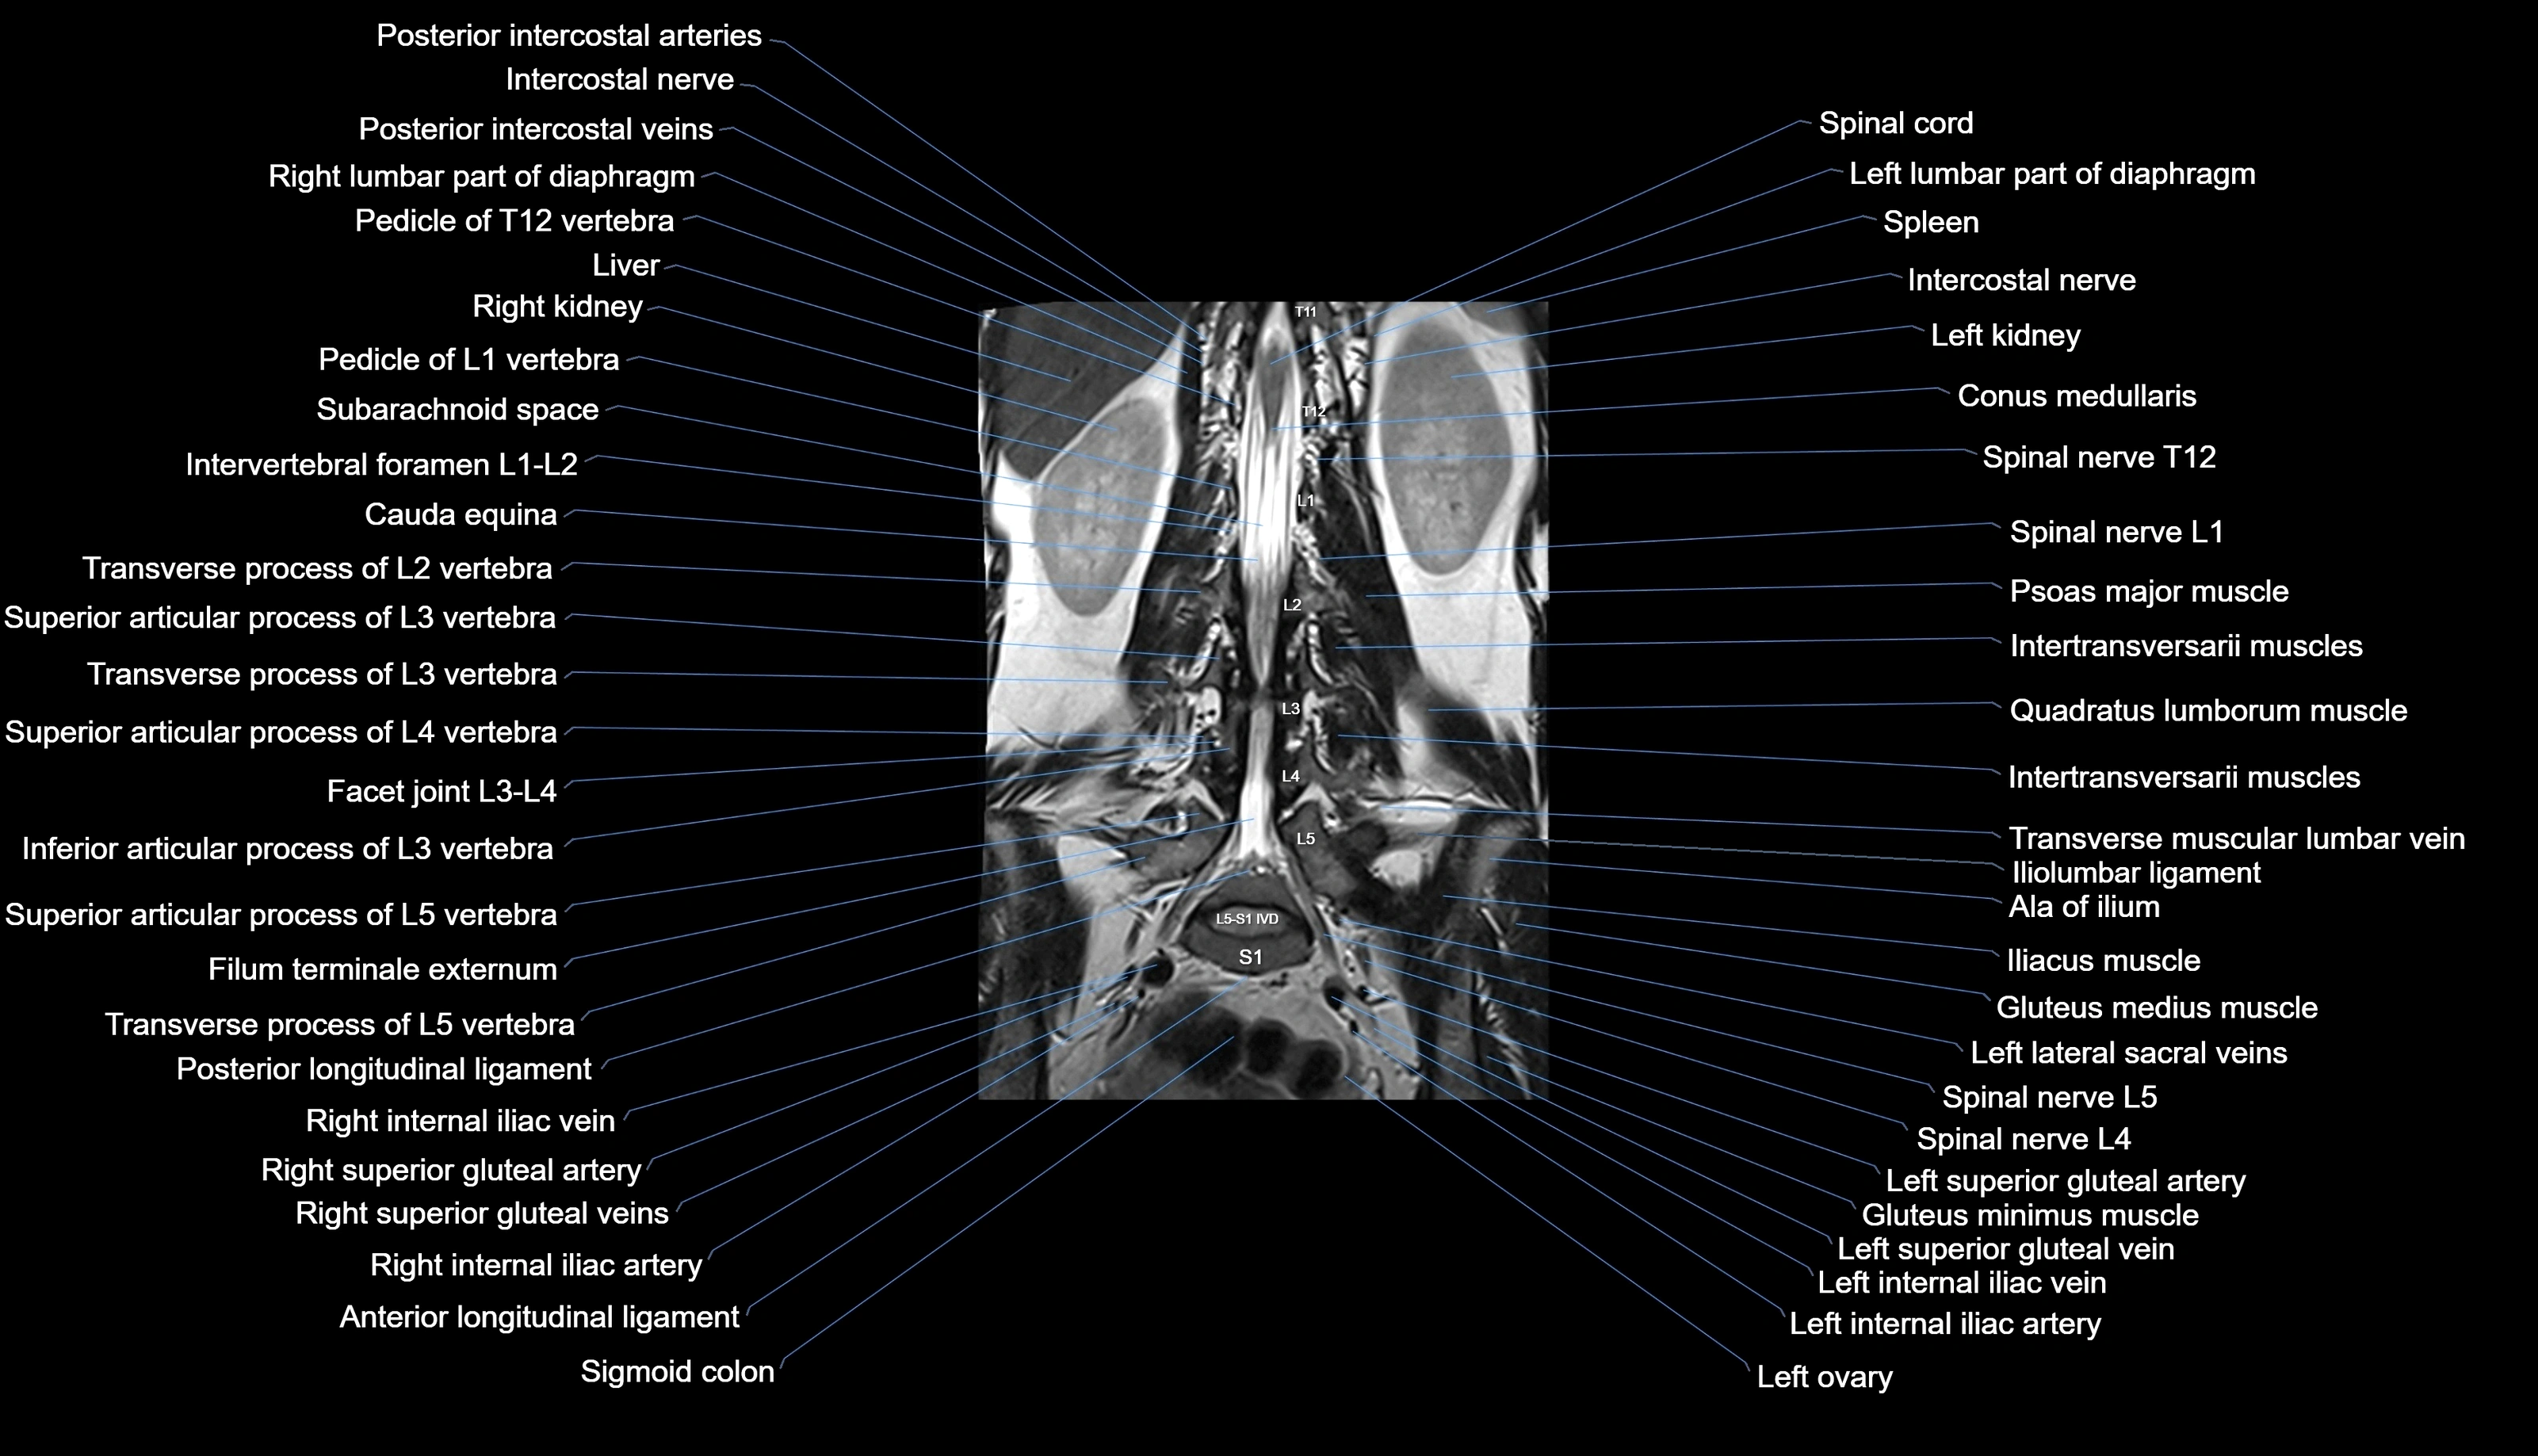

MRI images